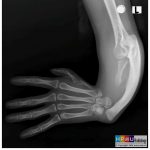

Gãy xương sườn là một tổn thương thường gặp trong chấn thương lồng ngực. Gãy trực tiếp: tác nhân gây chấn thương ở đâu thì xương sườn gãy ở đó. Đây là loại gãy từ ngoài vào, do đó tạng nào nằm ngay sát ổ gãy dễ bị thương tổn nhất (thường là phổi). Gãy gián tiếp: tác nhân gây chấn thương ép từ phía trước ngực, còn phía sau lưng là một vật cản cố định, lồng ngực bị ép dẹt lại theo chiều trước sau, cung bên của xương sườn sẽ bị gãy. Tạng nằm giữa trung thất là tạng dễ bị thương tổn (tim, mạch máu lớn)…